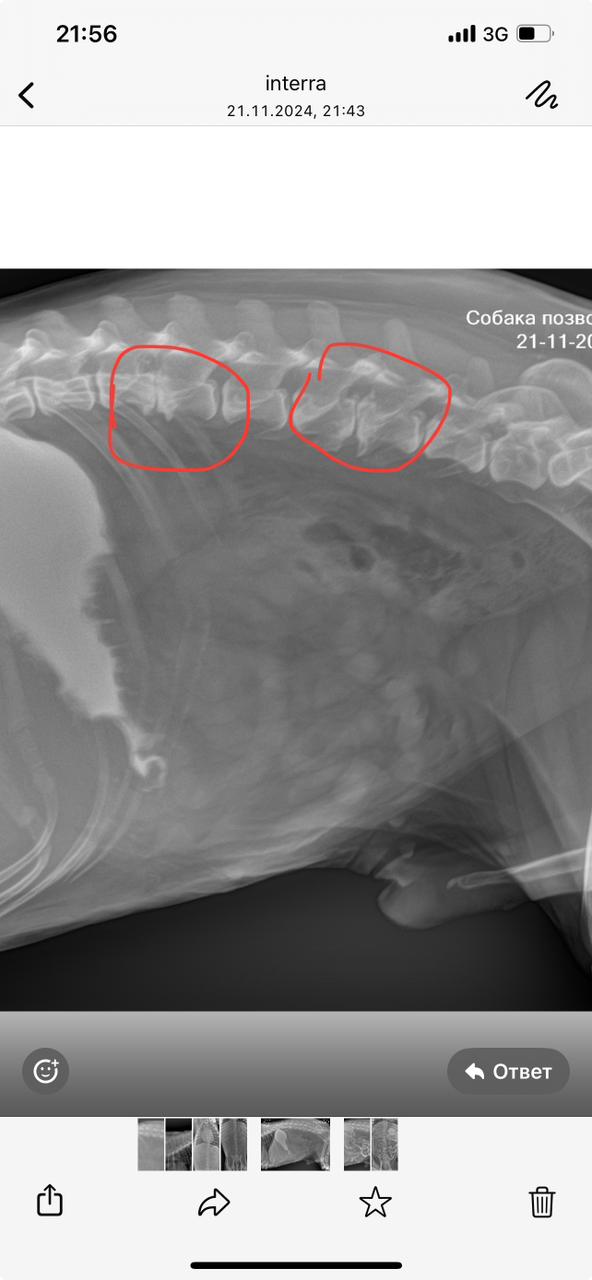

Рентген позвоночника

Вложения

IMG-20241121-WA0054.jpg

IMG-20241121-WA0047.jpg

IMG-20241121-WA0045.jpg

IMG-20241121-WA0034.jpg

IMG-20241121-WA0041.jpg